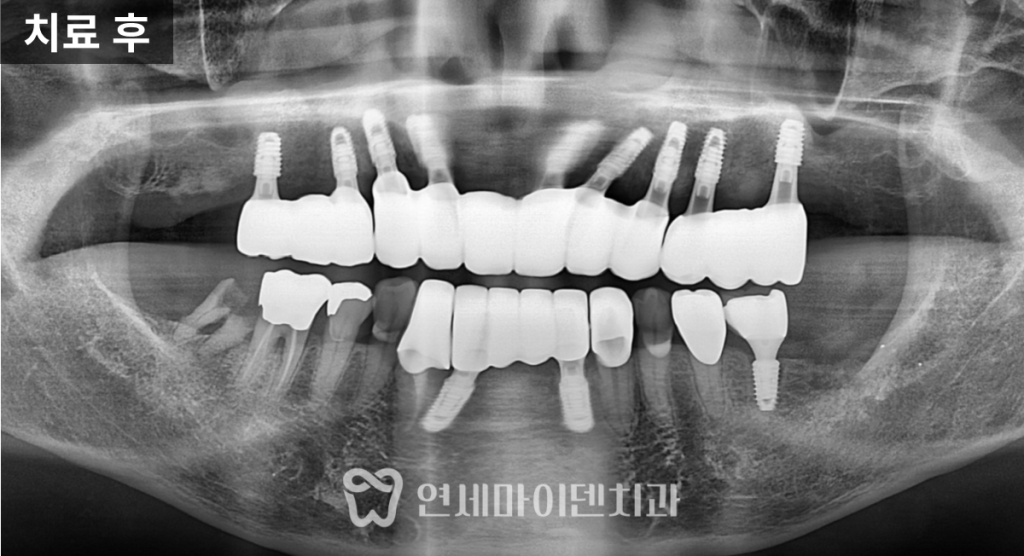

의도한 방향으로 조절할 수 있었습니다.치료 결과: 전치부 후방 이동과 기능 회복

치료 후

앞니는 약 5mm 내외로 후방 이동되었고,

위 앞니의 노출 비율이

이전보다 증가한 것을 확인할 수 있었습니다.어금니에서 교합이 안정적으로 지지되고,

전치부는 발음, 심미, 절단 기능을

균형 있게 수행하고 있었습니다.

측면에서

코–입술–턱 끝을 잇는 라인을 확인해도,

전치부가 후방으로 이동하며

입술 돌출이 완화된 모습이

객관적으로 확인되었습니다.

해당 케이스는

치료 후 2년이 지난 시점에서도

임플란트가 기능적·심미적으로

문제없이 사용되고 있었습니다.왜 ‘앞니부터’ 하면 안 될까요?